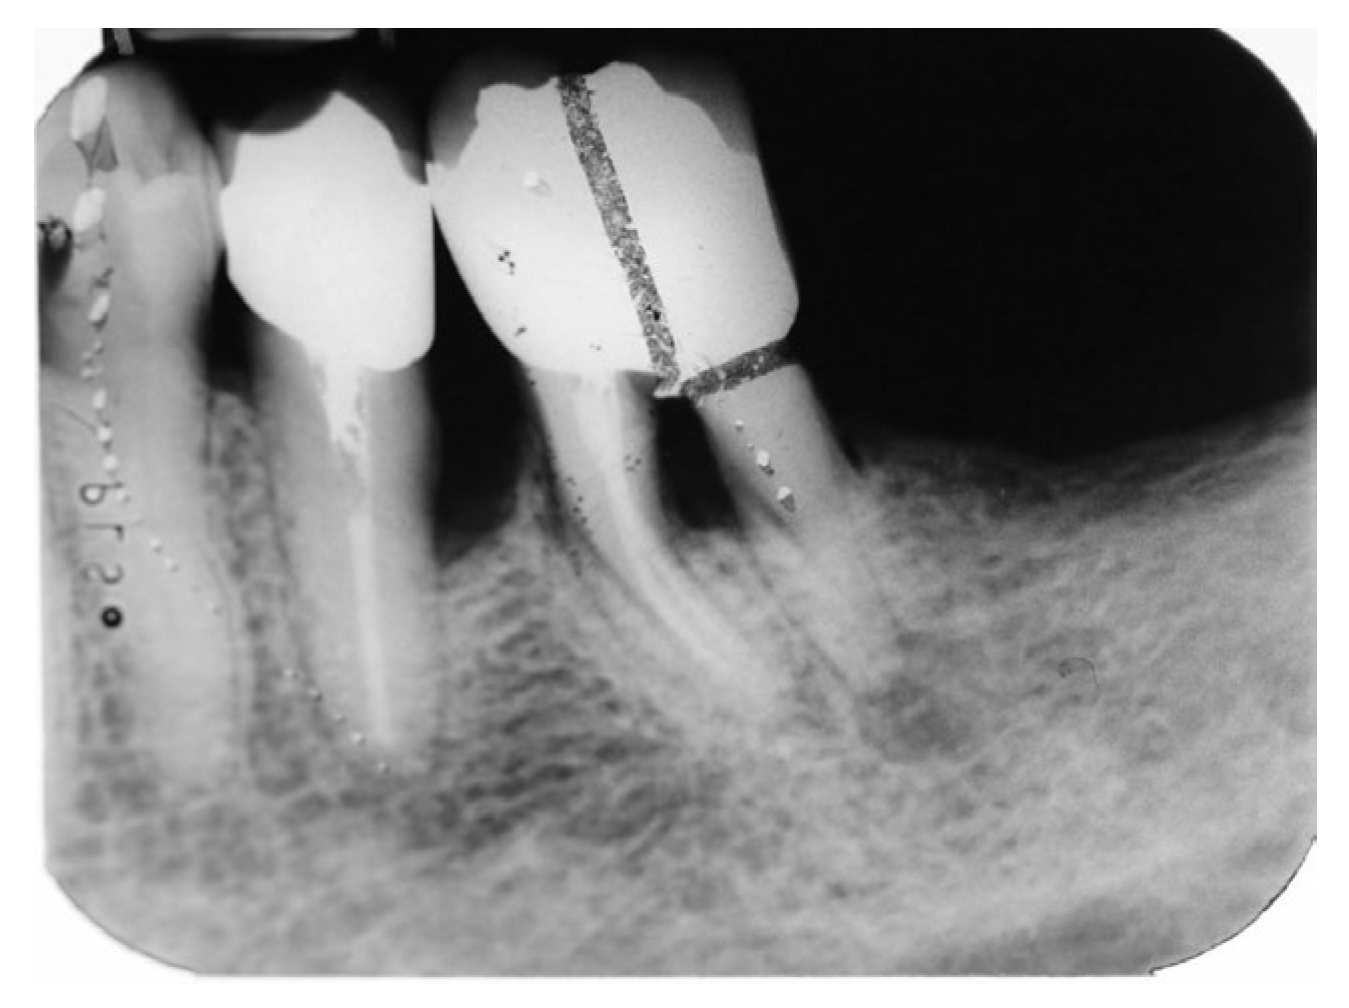

The treatment proceeded with hemisection of the first molar (#36), a full thickness mucoperiosteal flap was elevated and since the fracture was visible buccally, hemisection was performed using the vertical cut method, using a long-fissured diamond bur. The mesial root along with the equivalent part of the crown extracted using premolar forceps [4,12,13]. Sutures were places using 4-0 vicryl sutures. The patient was given verbally and written post-op instructions. After 10 days a recall appointment was scheduled. At the recall appointment normal socket and soft tissue healing was noted and the sutures were removed. After 15 days of sutures removal, the patient returned to office, the remaining abutment was shaped, and a provisional crown was manufactured chairside and cemented until proper healing of the socket occur. When healing was completed, preparation of the remaining tooth crown was finished, a special notch on distal occlusal surface on tooth #35 was made, an impression was done and a porcelain crown fused to metal having a mesial wing was manufactured. The mesial metal wing was designed to be bonded on the prepared notch on tooth #35. (Figure 13)

Figure 13. a) occlusal view of the dental cast b) dental crown placed on the cast c) dental crown with mesial wing d) occlusal view of the crown.